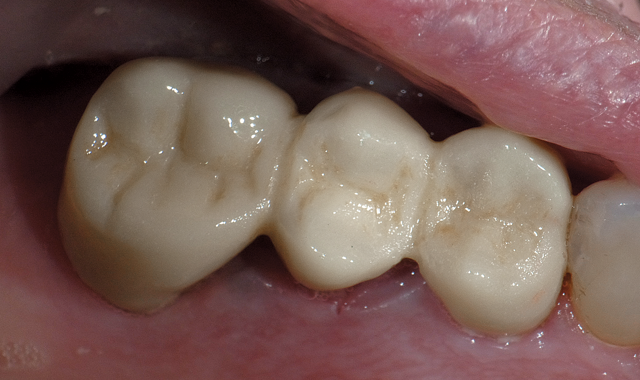

Fig. 4

Using periotomes from Dowell, the root is easily removed in an atraumatic fashion. The periotomes from Dowell are very thin, strong and flexible. The periotome is inserted between the root and surrounding bone and, as it moves apically, the periodontal ligaments are severed. The root is then removed using the root extractor provided in the Dowell kit. The socket is curetted to remove all remaining periodontal ligaments and establish bone bleeding. Demineralized freeze-dried bone is hydrated and placed in the socket. A collagen plug is cut to 2-4 mm in thickness and placed over the graft to contain it until a blood clot has formed. Sutures are not needed since the bridge pontic fits the extraction site perfectly and will keep the collagen in place. The plug also controls bleeding well enough to keep the preparations dry during cementation. The bridge is inserted and slight pressure is placed against the collagen plug. After the cement is set, the excess is removed.

The postoperative radiograph shows the margins of the restoration and the fill from the bone graft (Fig. 4). The bullet-shaped pontic design allows the pontic to appear as if it emerges from the tissue as a natural tooth. It also facilitates easy cleaning with floss.

Fig. 5

The ability to perform fixed bridge restorations with zirconia in a single visit is a tremendous advancement for both patients and dentists (Fig. 5). In conclusion: